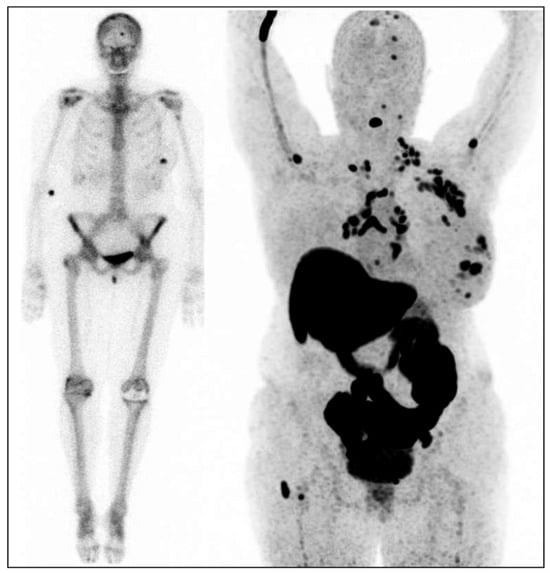

- Ibrahim, A.; Sakr, T.; Khoweysa, O.; Motaleb, M.; Abd El-Bary, A.; El-Kolaly, M. Radioiodinated anastrozole and epirubicin as potential targeting radiopharmaceuticals for solid tumor imaging. J. Radioanal. Nucl. Chem. 2015, 303, 967–975. [Google Scholar] [CrossRef]

- Binmujlli, M.A. Radiological and Molecular Analysis of Radioiodinated Anastrozole and Epirubicin as Innovative Radiopharmaceuticals Targeting Methylenetetrahydrofolate Dehydrogenase 2 in Solid Tumors. Pharmaceutics 2024, 16, 616. [Google Scholar] [CrossRef] [PubMed]